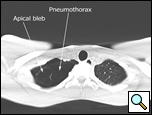

Patients who have had a second episode of spontaneous pneumothorax are those most likely to be considered for thoracoscopic pleurectomy and apical blebectomy. However, patients with a first episode of spontaneous pneumothorax who have a prolonged air leak (greater than 72 hours), incomplete expansion of the lung (Figure 1), bilateral pneumothoraces, associated hemothorax, tension pneumothorax (Figure 2), or a bleb on their CT scan (Figure 3) should be offered surgery at the time of the first occurrence [1]. Patients who have had a spontaneous pneumothorax and whose occupation places them at risk for a second episode or places them in a situation where medical intervention is not readily accessible should be considered for surgery. Therefore divers, pilots, submarine personnel, and those that work or live in the wilderness or space are suitable patients [1].

| Figure 1: Chest x-ray showing incomplete expansion of lung after chest tube placement. | Figure 2: Chest x-ray showing tension pneumothorax with mediastinal shift. | Figure 3: CT Scan showing apical bleb. |